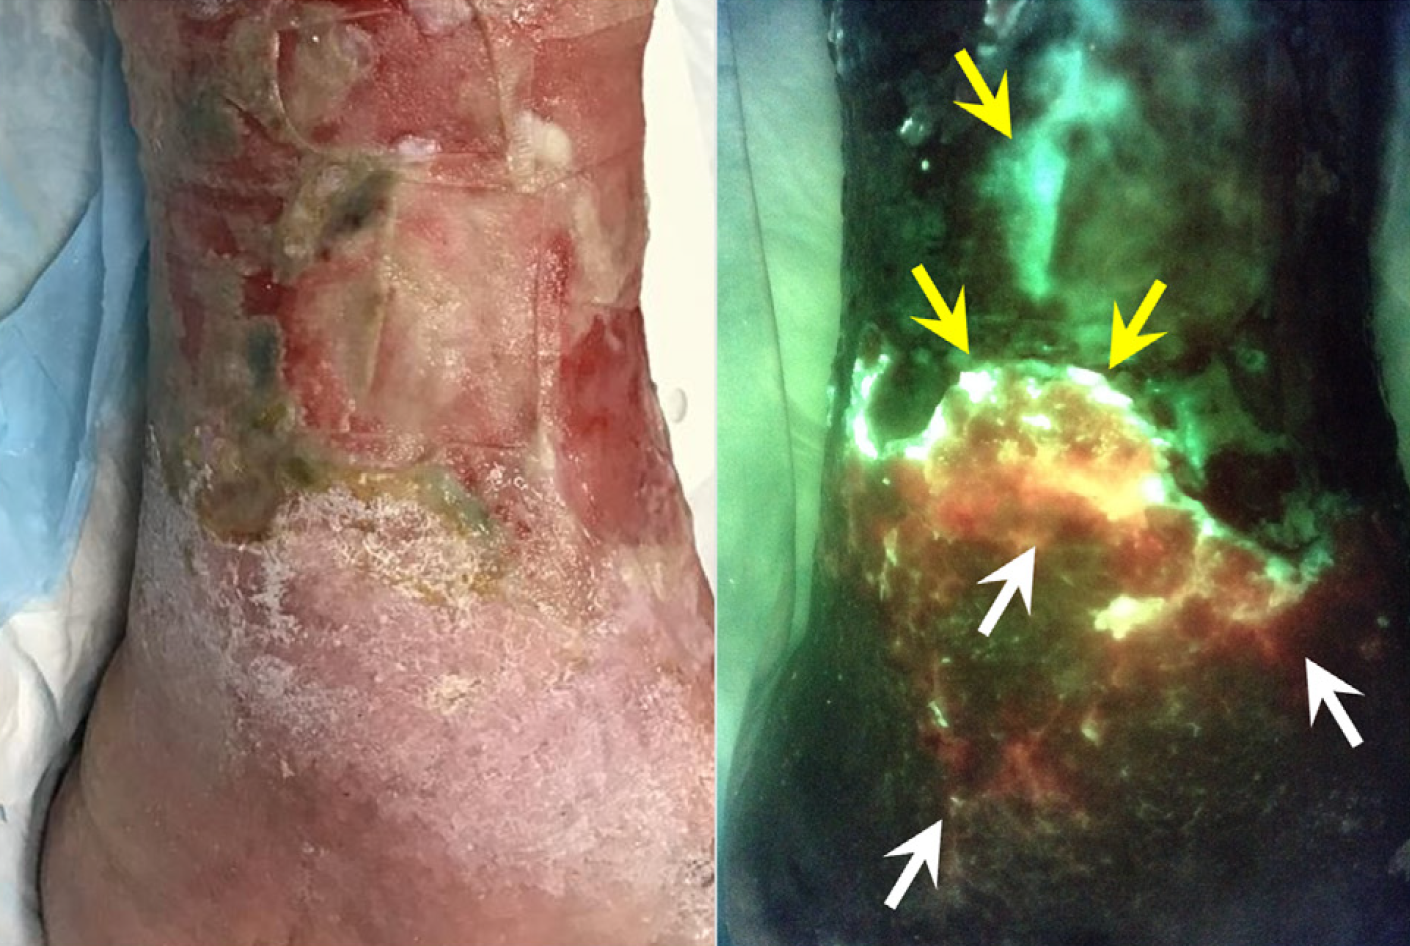

Diagnosis and treatment of the invasive extension of bacteria (cellulitis) from chronic wounds utilizing point-of-care fluorescence imaging

Andersen, A. et al. Int Wound J 2021